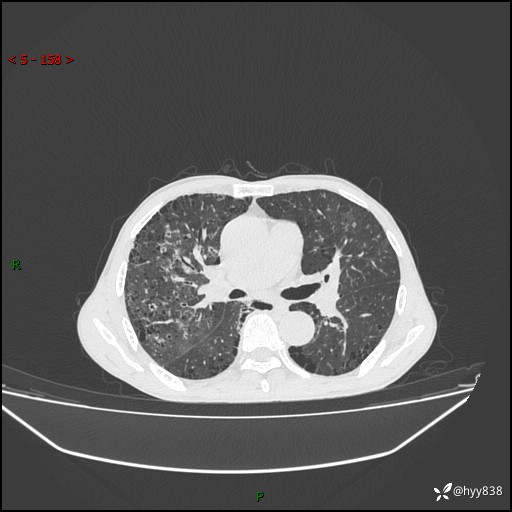

胸部CT平扫